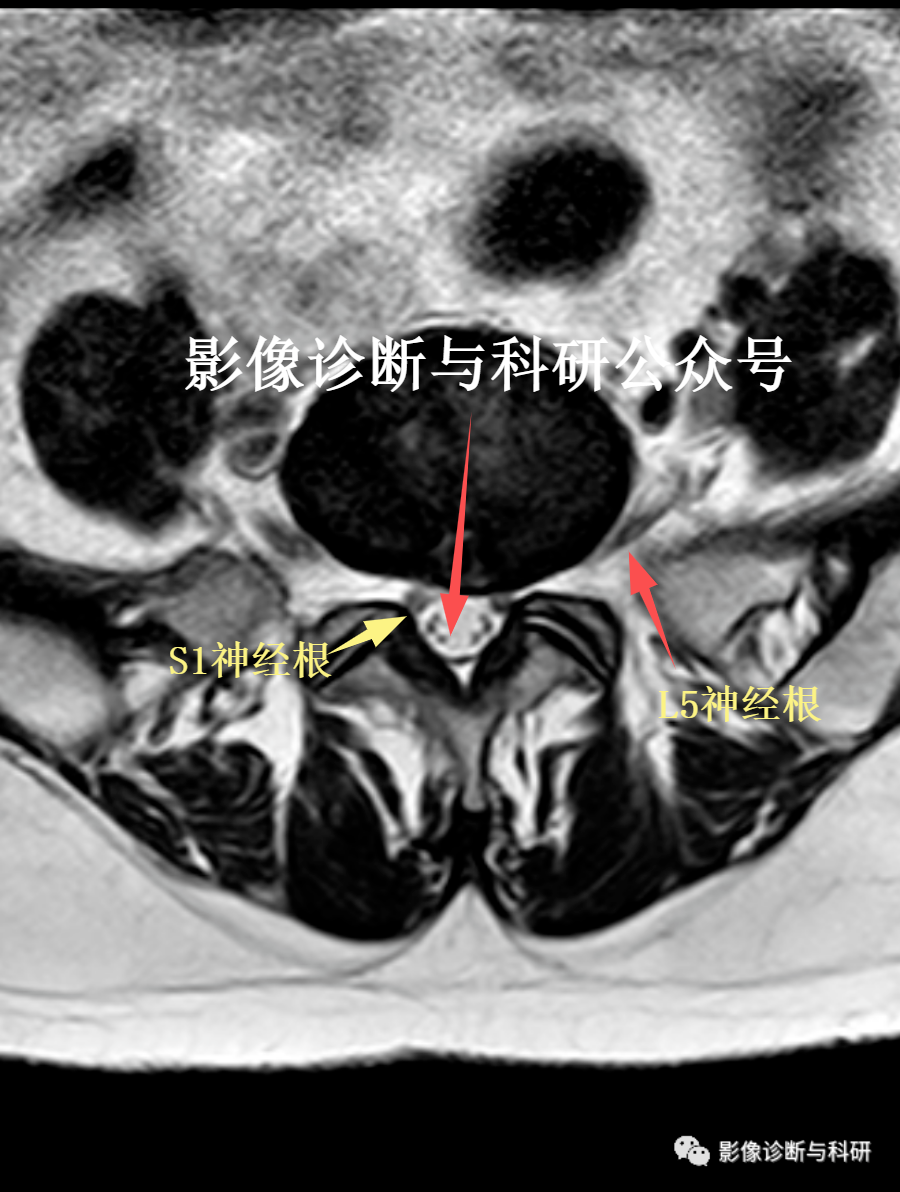

5.神经根受压

椎间盘向侧后方突出时,可造成神经根的受压,在横断面上显示较好,可观察到侧隐窝饱满,神经根淹没,或突出髓核突入椎间孔,推移椎间孔内脂肪,压迫神经根。

L4神经通过L4/5孔从L4椎骨下方伸出,L4/5层面后方椎管内见L5及S1神经根下行。